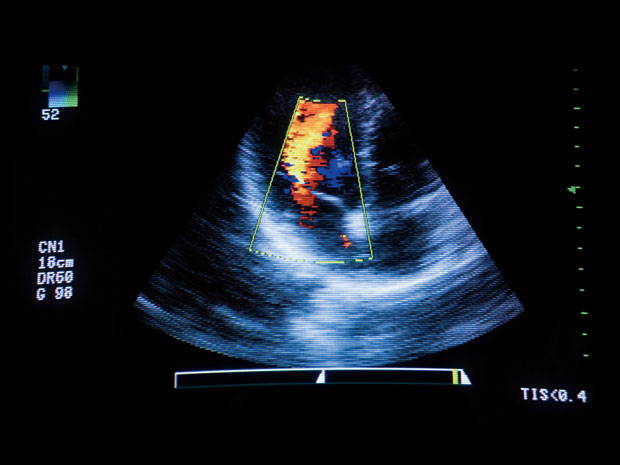

일부 임산부에서 '본인부담금 역전현상'이 벌어지면서 논란이 됐던 임산부 초음파 급여화 조치와 관련, 정부가 후속 대책을 모색키로 했다. 급여기준 세부사항을 통해 대안을 마련하겠다는 입장이다.

2일 보건복지부 출입기자협의회 취재결과, 복지부는 오는 4일 건강보험심사평가원 서울사무소에서 건강보험정책심의위원회를 열어, 임산부 초음파 급여기준 세부 개선안 등을 논의키로 했다.

산전 초음파 급여화가 시행된 것은 지난달 1일. 그러나 급여화 조치 이후 일부 산모들의 비용부담이 오히려 늘어나면서 불만의 목소리가 나왔다. 관행수가에 크게 못미치는 비급여 수가를 받았던 일부 의료기관에서, 급여화 이후 오히려 산모의 부담이 늘어나는 현상이 목격된 것.

이는 지난 국정감사에서도 이슈가 됐으며, 일부에서는 "임산부들의 초음파 검사 비용 부담 완화라는 취지를 달성하려면 초음파 검사 비용에 대한 본인부담률을 하향조정하는 방안을 검토하라"는 등의 제도개선 주문이 잇달았다.